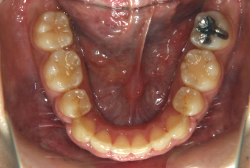

叢生(そうせい)

凸凹な歯並びのことを叢生といいます。矯正歯科に来院する患者様の主訴の中で、最も多いのが「配列の凸凹を真っ直ぐにしたい」というものです。歯の大きさと顎の大きさの調和がとれていないことが原因です。

凸凹を主体としたケースの場合、当院の平均治療期間は18ヶ月ですので、このケースは少し長めに経過しました。理由の一つは凸凹の程度がかなり重症だったと言うことですが、もう一つは、右下第2大臼歯が45度くらい前傾していたため、それを整直化させるために時間を要したと考えています。いずれにしても最終結果は大変よい状態と思います。

治療前は並びが乱れて見た目が悪いというのはもちろん問題ですが、歯科医学的に一番困るのは噛み合わせが悪いという点です。上下の犬歯(3番目の歯)は、上下的に離れた位置にあるため接触することができません。つまり歯としては存在していても、歯としては機能していないということです。